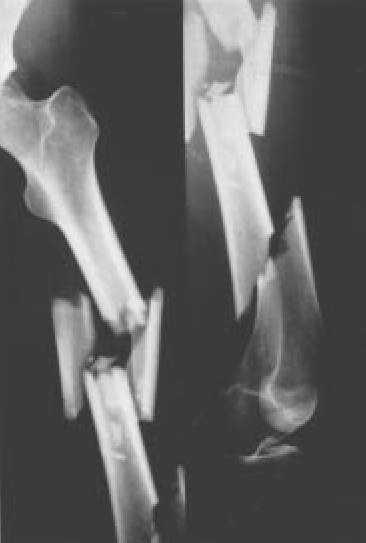

Fig. 6.: Proyección anteroposterior y lateral de una fractura diafisaria de fémur con severa conminución